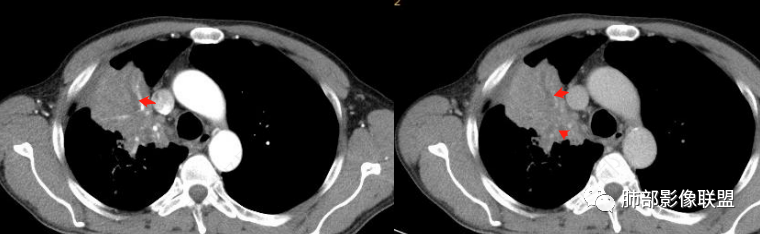

下图:这是中央型肺癌的特点:肺动脉破坏。

腔内肿瘤?肺动脉没有推移,累及多段